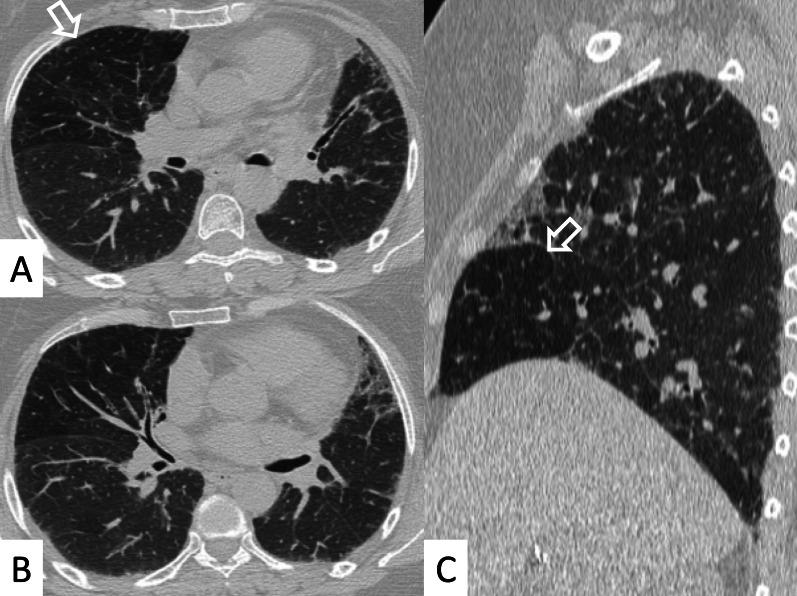

Connective tissue diseases (CTDs) include a spectrum of disorders that affect the connective tissue of the human body; they include autoimmune disorders characterized by immune-mediated chronic inflammation and the development of fibrosis. Lung involvement can be misdiagnosed, since pulmonary alterations preceded osteo-articular manifestations only in 20% of cases and they have no clear clinical findings in the early phases. All pulmonary structures may be interested: pulmonary interstitium, airways, pleura and respiratory muscles. Among these autoimmune disorders, rheumatoid arthritis (RA) is characterized by usual interstitial pneumonia (UIP), pulmonary nodules and airway disease with air-trapping, whereas non-specific interstitial pneumonia (NSIP), pulmonary hypertension and esophageal dilatation are frequently revealed in systemic sclerosis (SSc). NSIP and organizing pneumonia (OP) may be found in patients having polymyositis (PM) and dermatomyositis (DM); in some cases, perilobular consolidations and reverse halo-sign areas may be observed. Systemic lupus erythematosus (SLE) is characterized by serositis, acute lupus pneumonitis and alveolar hemorrhage. In the Sjögren syndrome (SS), the most frequent pattern encountered on HRCT images is represented by NSIP; UIP and lymphocytic interstitial pneumonia (LIP) are reported with a lower frequency. Finally, fibrotic NSIP may be the interstitial disease observed in patients having mixed connective tissue diseases (MCTD). This pictorial review therefore aims to provide clinical features and imaging findings associated with autoimmune CTDs, in order to help radiologists, pneumologists and rheumatologists in their diagnoses and management.

结缔组织病(CTDs)包括一系列影响人体结缔组织的疾病;它们包括以免疫介导的慢性炎症和纤维化发展为特征的自身免疫性疾病。肺部受累可能会被误诊,因为肺部改变仅在20%的病例中先于骨关节炎表现出现,且在早期阶段没有明确的临床发现。所有肺部结构都可能受累:肺间质、气道、胸膜和呼吸肌。在这些自身免疫性疾病中,类风湿关节炎(RA)的特征是普通型间质性肺炎(UIP)、肺结节和伴有空气潴留的气道疾病,而系统性硬化症(SSc)常表现为非特异性间质性肺炎(NSIP)、肺动脉高压和食管扩张。NSIP和机化性肺炎(OP)可见于多发性肌炎(PM)和皮肌炎(DM)患者;在某些情况下,可观察到小叶周围实变和反晕征区域。系统性红斑狼疮(SLE)的特征是浆膜炎、急性狼疮性肺炎和肺泡出血。在干燥综合征(SS)中,HRCT图像上最常见的表现是NSIP;UIP和淋巴细胞间质性肺炎(LIP)的报道频率较低。最后,纤维化NSIP可能是混合性结缔组织病(MCTD)患者中观察到的间质性疾病。因此,本图像综述旨在提供与自身免疫性CTDs相关的临床特征和影像学表现,以帮助放射科医生、呼吸科医生和风湿病科医生进行诊断和管理。